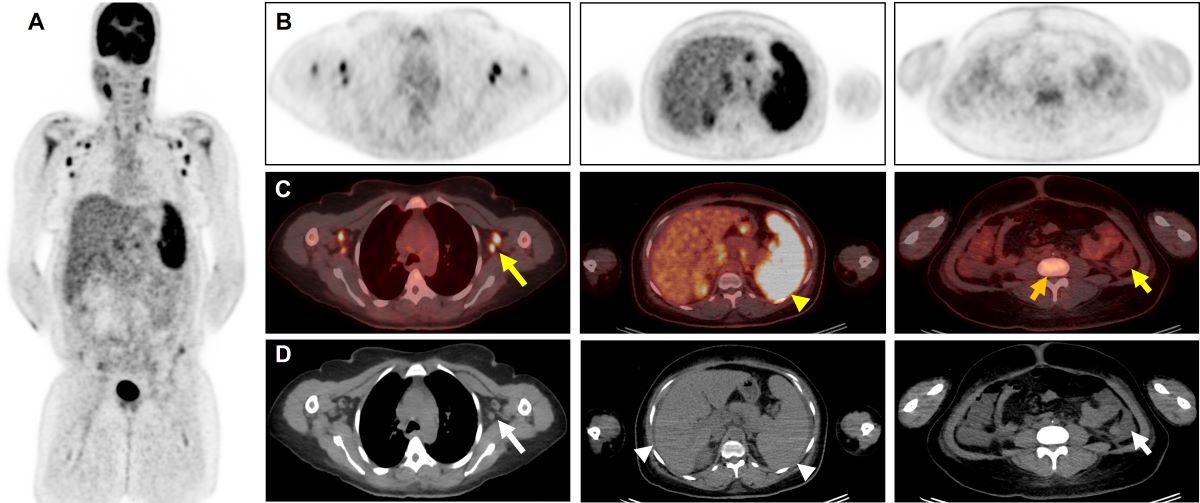

- Behnia F, Elojeimy S, Matesan M, Fajgenbaum DC. Potential value of FDG pet-CT in diagnosis and follow-up of TAFRO syndrome - annals of hematology [Internet]. Springer Berlin Heidelberg; 2016.

- Hotta M, Minamimoto R, Yashima A, Nakano M, Yamashita H. FDG PET/CT findings in TAFRO syndrome. Clinical Nuclear Medicine. 2018. [CrossRef]